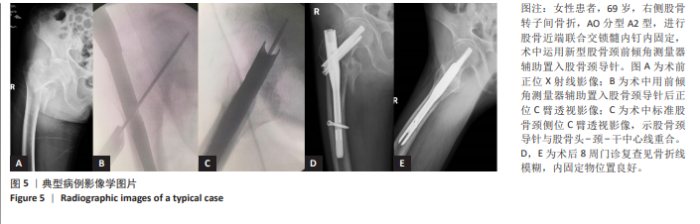

METHODS: Based on Brunner's method for measuring femoral neck anteversion, a digital model of the femoral anteversion angle measuring device was designed and 3D-printed. A surgical model was constructed using anatomically scaled human femur phantoms and auxiliary structures to simulate intertrochanteric fracture fixation for intertrochanteric fractures on a traction bed. The 3D-printed prototype was utilized to assist guide needle insertion. Three groups of femur models were tested, with experimental data recorded and statistically analyzed. The device design was optimized, and a physical prototype was produced. Twenty patients with intertrochanteric femoral fractures were prospectively enrolled (trial group: n=10, control group: n=10). The trial group underwent guide needle placement assisted by the measurement device, while the control group received conventional treatment by the same surgical team. Comparative analysis of surgical parameters was conducted to evaluate device efficacy and clinical utility.

RESULTS AND CONCLUSION: (1) The novel femoral neck anteversion angle measurement device (Patent No. ZL202120806525.X) enables real-time measurement of the anteversion angle of the proximal guide frame during intramedullary nailing. (2) The novel anteversion angle measurement device can accurately reflect the femoral neck anteversion measured by Brunner's method and indicate the required proximal guide frame angle for guide needle insertion. (3) Clinical trial results showed that compared with the control group, the trial group had shorter surgical time (P=0.042), less femoral neck guide wire deviation (P=0.001), fewer fluoroscopy sessions, fewer repeated guide wire placements, and shorter guide wire placement time (P < 0.05). (4) The novel anteversion angle measurement device can accurately measure and indicate the anteversion angle of the femoral neck guide wire during real-time intraoperative use. It can be used with a variety of proximal femoral intramedullary nail fixation device systems, does not directly contact the human body, and does not cause additional damage, making it valuable for clinical promotion.